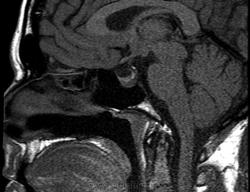

Ж, 37 лет. Наблюдается по поводу микроаденомы гипофиза, исследование в динамике. Предыдущие снимки сделаны в другом учреждении около года назад, картинка примерно такая же, однако на пленке отсроченные и постконтрастные снимки отсутствуют. В заключении была обозначена микроаденома округлой формы 3мм в диаметре.

Вот такая интересная картинка у нас получилась:

T2

Не полупустой, в нижних отделах странной формы аденома. Плоская какая-то. За аденому то, что она хоть и медленно, но накапливает контраст, который в ней задерживается после того, как уже почти полностью вымылся из здоровой паренхимы аденогипофиза. Полупустой гипофиз (вернее полупустое турецкое седло, ещё вернее вторично "пустое" турецкое седло) получается после удаления аденомы. Или после самопроизвольного опорожнения кисты/кистозной аденомы гипофиза. 2 часа назд такое контролировал.

Честно говоря, я сначала подумал, что гипофиз как будто "висит" над дном турецкого седла, а под ним - жидкость. После контрастирования действительно - аденома.

Нет, оказалось, что это вовсе не жидкость, а по характеру накопления парамагнетика - аденома необычной формы и локализации.